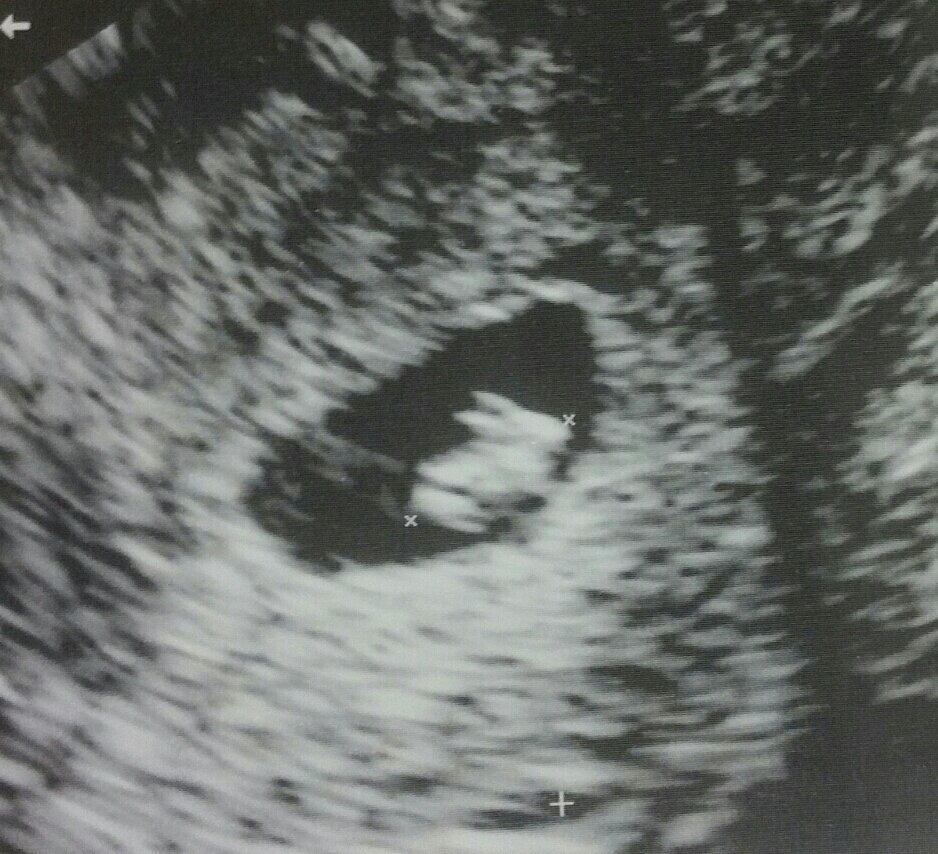

Đa số mẹ bầu tới tuần thứ 7 đã có yolksac, tức là túi noãn hoàng và có phôi thai rồi. Nhưng một số trường hợp thai 7 tuần có yolksac nhưng chưa có phôi thai, có thể là do thai phát triển chậm, phôi thai có thể đã hình thành nhưng còn quá nhỏ nên siêu âm chưa nhìn rõ được và mẹ cần chờ thêm để phôi thai lớn hơn. Nhưng cũng có những trường hợp đáng tiếc có thể xảy ra nếu chưa thấy phôi thai ở tuần 7. Vì vậy cũng giống như với vấn đề tim thai, mẹ hãy làm theo chỉ dẫn của bác sĩ sau khi khám thai cụ thể nhé.

Thai nhi 7 tuần tuổi đã có những bước phát triển nhất định cả về hình dáng bên ngoài cũng như các chức năng bên trong của cơ thể. Chính vì thế, đây là giai đoạn thích hợp để mẹ bầu tiến hành siêu âm hình ảnh thai nhi và kiểm tra quá trình phát triển của bé yêu. Hình ảnh siêu âm thai 7 tuần tuổi sẽ cho biết nhiều chỉ số sức khỏe quan trọng giúp mẹ hình dung rõ ràng, cụ thể mức độ phát triển của bé yêu vào thời điểm này.